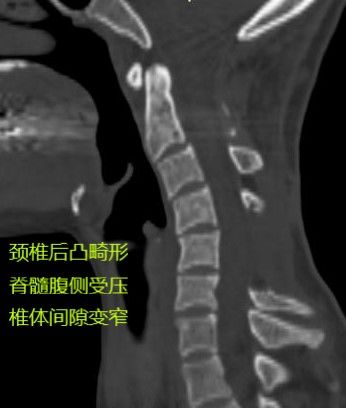

前次手术患者仅被移除C5椎板和棘突,就发生显著脊柱畸形。

周迎春教授考虑到患者不仅有椎管内外占位的问题,还合并脊柱畸形,而要完整切除肿瘤必须打开左侧椎间孔,将使得脊柱畸形进一步加重,于是为患者制定了前后路联合手术方案:切除肿瘤+脊柱矫形。

术后CT见颈椎曲度和椎体间高度恢复满意。